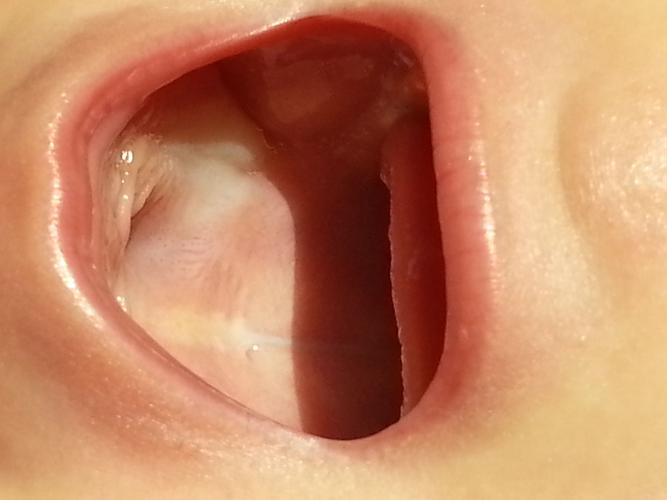

宝宝口腔上颚内壁发白

马牙(Epstein pearls)

- 特征:在宝宝上颚中线附近或牙龈边缘,出现一些白色或黄白色的小颗粒,像米粒或小沙子一样,大小不一,数量可能是一个或多个。

- 成因:这是胚胎发育时期残留的上皮细胞堆积形成的,是一种正常的生理现象。

- 处理:完全不需要处理! 这些“马牙”会随着宝宝吃奶、吸吮等动作摩擦,在几周或几个月内自行脱落,不会影响宝宝吃奶和口腔健康,千万不要用针或布去挑破,以免造成感染。